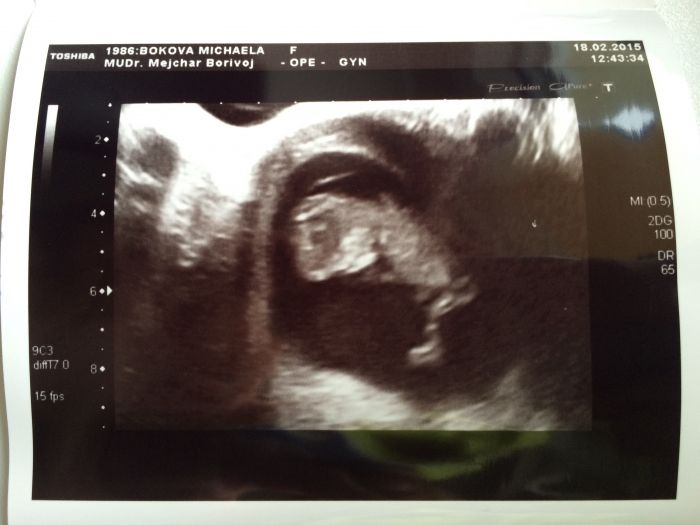

Lucii, krásná fotečka, nefotil to můj doktor? mám skoro stejnou, z 10.tt...Cool

Ahoj holky a pane :) moc vam vsem gratuluji k výsledkům. Mimísům se daří :) ja byla na kontrole minulou stredu, dnes jsem 12+4. Ultrazvuk v poradku a výsledky genetiky jeste nevim, ale uz je to tyden, tak snad uz by se ozvali. Na pristi kontrolu jdu 25.3., to uz se snad dovime i pohlaví :) chtela jsem se zeptat co si myslíte o tom druhem screeningu? Pry nebývá tak přesný a dost často tak akorat stresuje.. Taky prikladam foto mimi :) mějte se všichni moc fajn!

Jeste to foto :)